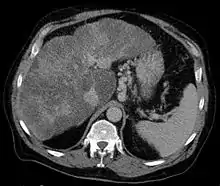

| Isolated gastric varices of Sarin classification IGV-1 seen on gastroscopy in a patient with portal hypertension | |